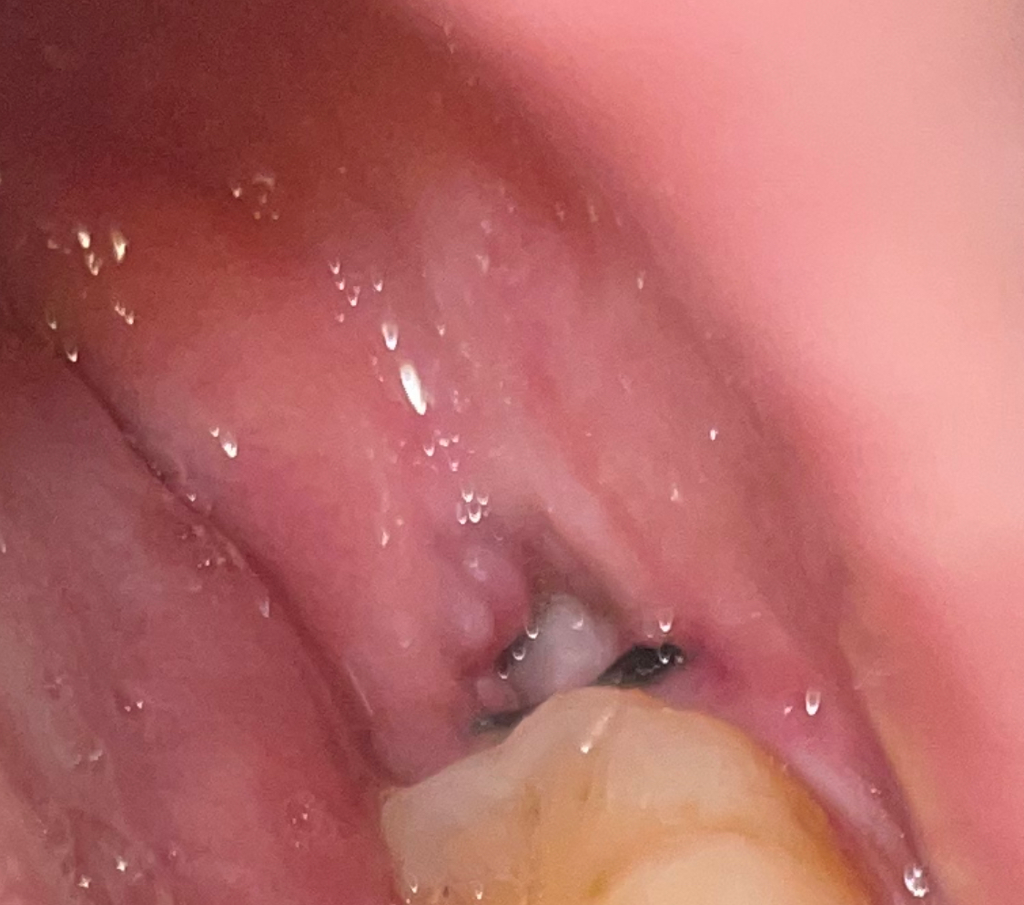

사랑니 발치 3일차 드라이소켓인가요?

ㅠㅠ 발치 후 통증이 거~의 없었고 아침에 일어나면 살짝.. 진통제 안 먹으면 살짝.. 있는 정도 입니다.. 경각심을 모르고 하지말라는 거 다 했었는데 갑자기 너무너무 걱정이 되어 여쭤봅니다..

드라이소켓 가능성 있을까요?

보여주신 사진으로서는 드라이소켓의 소견은 보이지 않습니다. 드라이소켓이라면 지금 말씀하시는 이상의 통증 및 불편감입니다. 즉 글을 쓰지 못할 정도로 통증이 심하기 때문에 말씀하신 정도의 통증은 드라이소켓과 거리가 멉니다.

드라이소켓이 있으면 통증이 매우 심하고 악취가 많이 납니다.

사진상으로 별 문제는 모르겠지만 혹시 증상이 있으면 치과를 가시는게 좋습니다.

사진상으로 보면 드라이 소켓은 아닌거 같습니다. 드라이소켓은 감염의 일종으로 냄새도 많이 나도 극심한 통증이 잇습니다.

드라이소켓은 보통 아래쪽 사랑니 발치후 24~48시간 사이에 갑자기 발생하고 발치와의 뼈와 신경이 그대로 외부에 노출됩니다..드라이소켓은 약으로 조절되지 않는 통증, 발치한 부위에서 얼굴 전체로 퍼지는 통증이 있습니다..드라이소켓으로 보여지지 않으니 염려 안해도 될것 같습니다.